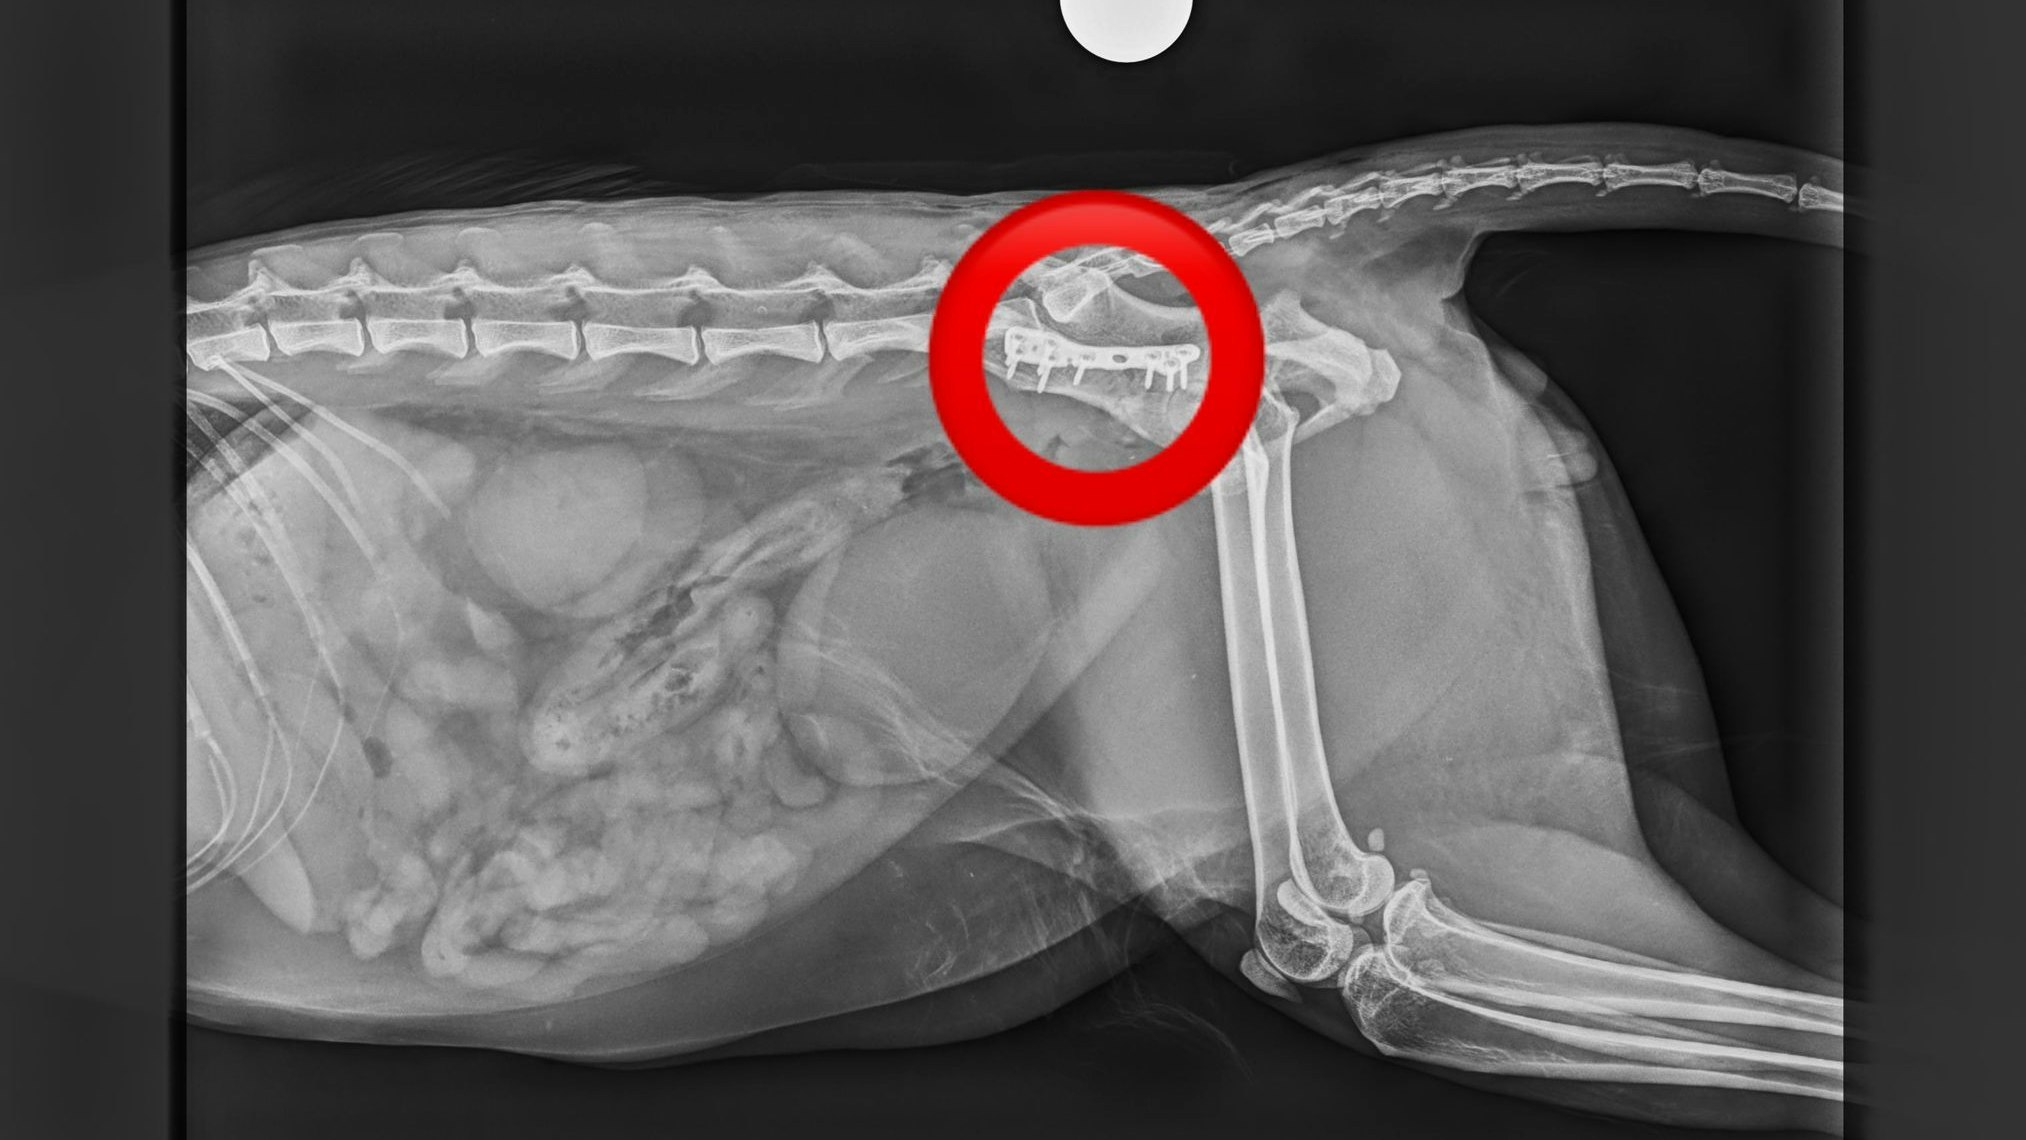

Ein schwarzer Kater hatte großes Glück und konnte noch rechtzeitig im oberösterreichischen Mondsee gefunden werden. Er hat schwere Verletzungen, die entweder auf einen Autounfall oder einen schweren Sturz hindeuten, und wird zurzeit über den Tierschutzhof der Pfotenhilfe in Lochen bei dem orthopädischen Chirurgen Tierarzt Mag. Daniel Eschlböck stationär medizinisch versorgt und gepflegt.

Der Kater erlitt multiple Beckenbrüche.

©Pfotenhilfe